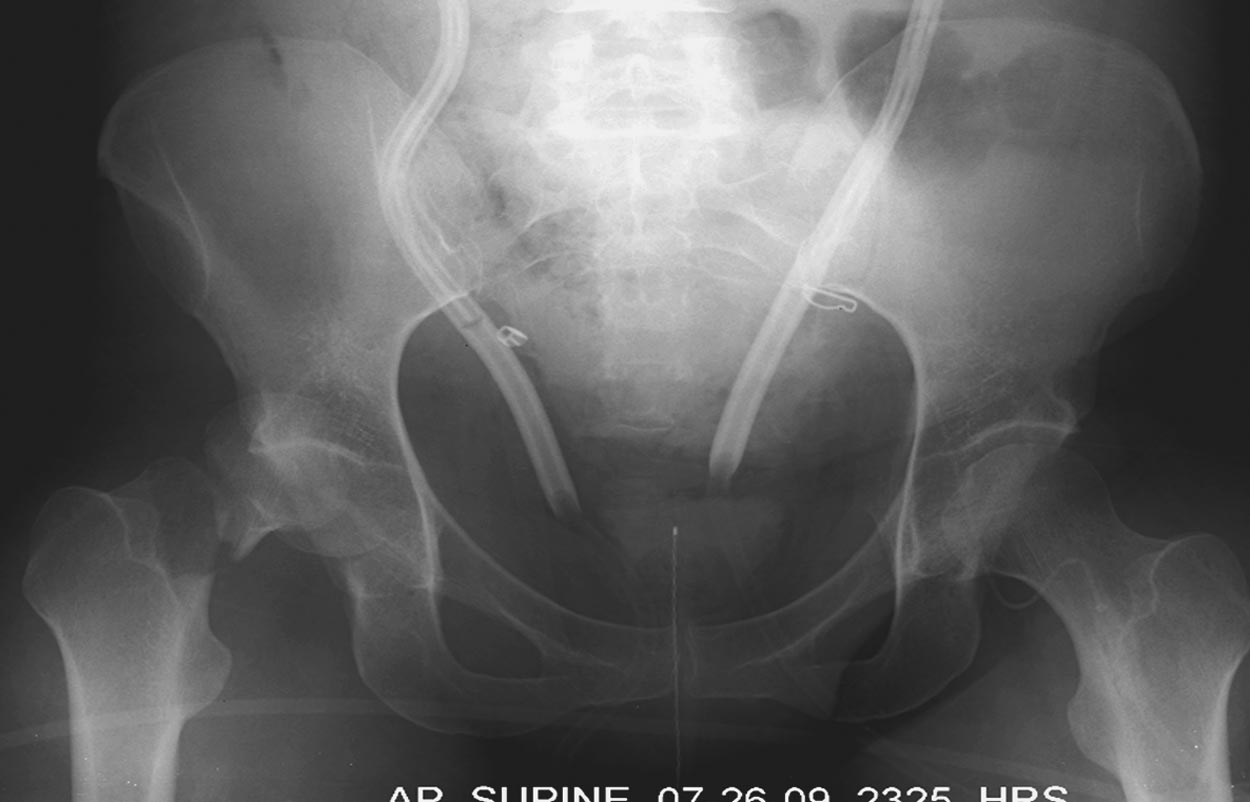

Травма хирург принял решение продолжать лечение в операционной. Срочная диагностическая лапаротомия с абдоминальной тампонадой, переливание 5 единиц крови. Irrigation & Debridement открытых ран с вакуумированием, попытка закрытой репозиции деформации сустава. По-прежнему состояние тяжелое, но давление стало стабилизироваться. Смогли получить первые диагностические данные.

Здесь перечислены ортопедические повреждения: Rt. femoral shaft fracture, Rt femoral head fracture-dislocation, Rt distal femur fracture, Rt. open patella fracture, Rt. talus fracture dislocation, Rt. open humerus fracture, Left 5th metatarsal fracture, Left dislocation 1st TMT.

Курс реанимации продолжается, вливания кристаллоидов и эритроцитарной массы стали действовать положительно. Остается под интубацией, но стал отвечать на команду!

6 день госпитализации-операция на таранной кости.

Результат раневого посева отрицательный на инфекцию. Остается фиксировать остальные повреждения: проксимальное бедро, открытые переломы бедра, плеча. Какие предложения?

На 25 день с момента травмы операция на Jackson table с боковым обширным доступом. Удаление стержней с местной обработкой. В тазобедренном суставе удаление головки, на дне вертлужной впадины полная отслойка хряща. Вертлужный компонент с одним винтом и короткая ножка - Fitmore press fit stem. На второй день однократно доза радиации для профилактики гетеретопической оссификации. Послеоперационный период без температуры. Выписана. Нагрузку разрешили на левой стороне, а полная в 3 мес. Здесь снимки при амбулаторном наблюдении: послеоперационно, 2 мес, 3 мес и 6 мес. Нагрузка полная, отсутствует хромота, и нет жалоб.